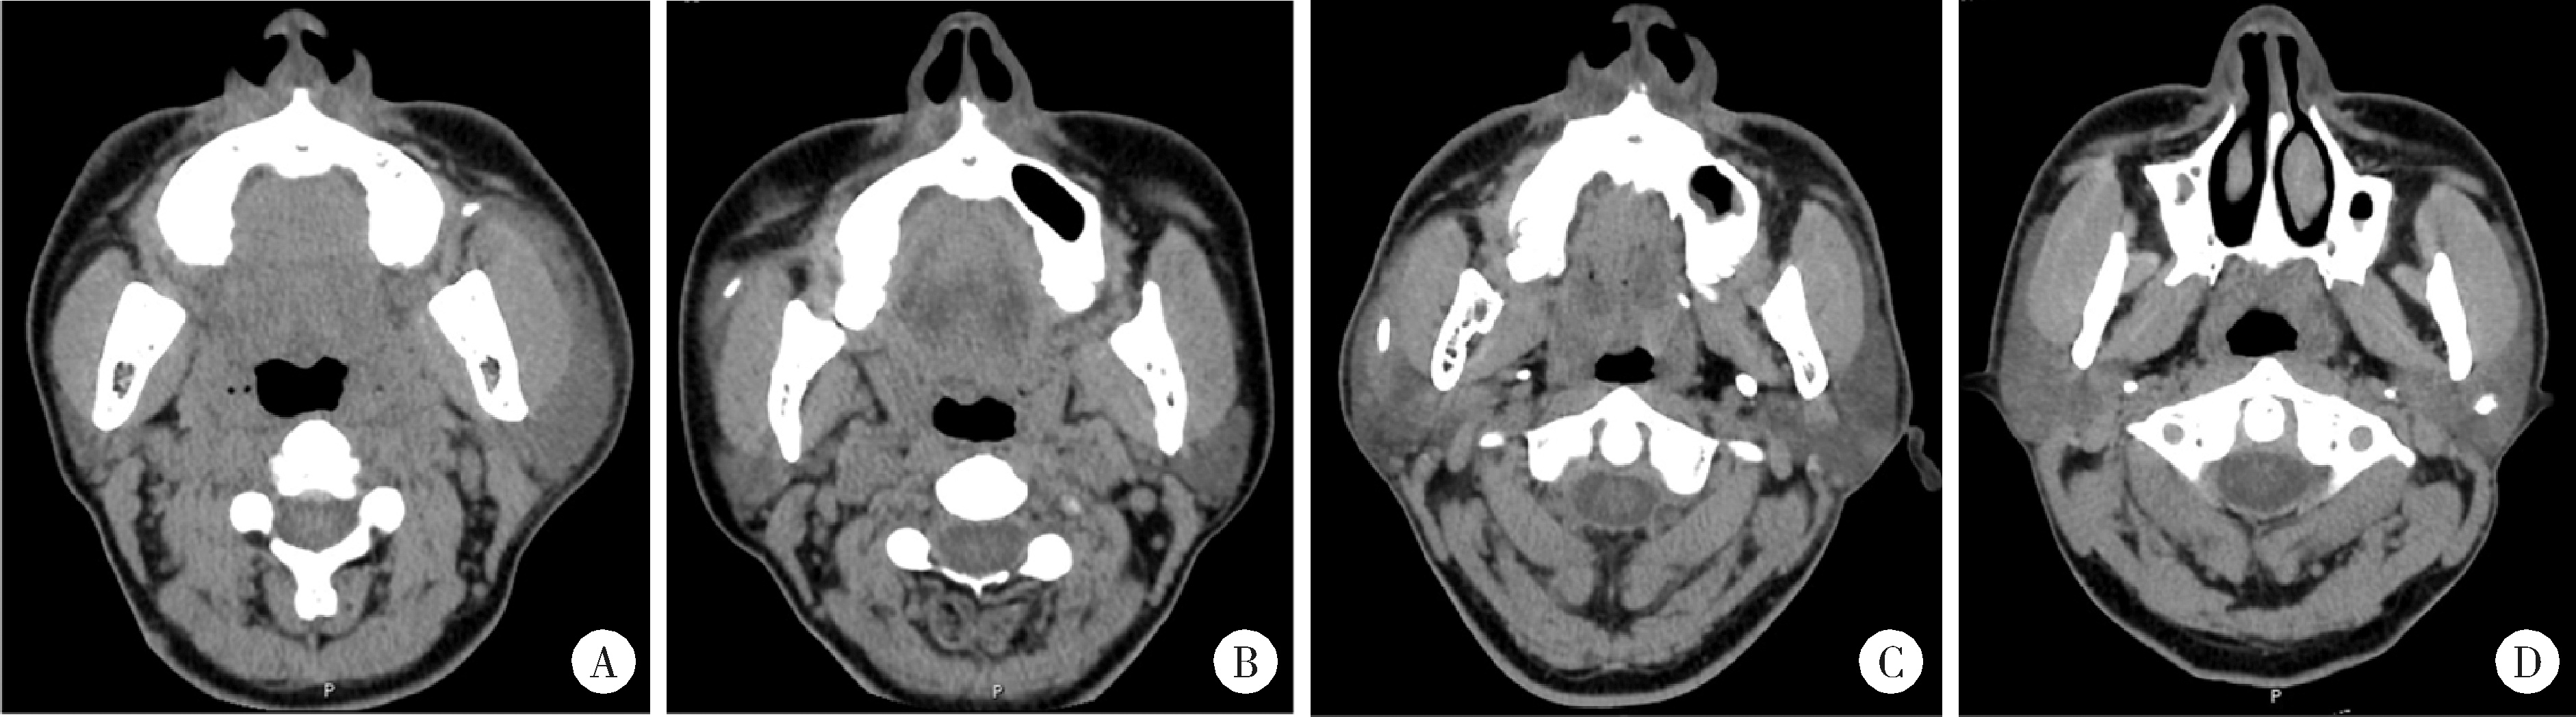

Figure 1

Axial images of spiral CT showing the calculi in the parotid duct system A, calculus in the anterior segment of the left parotid duct; B, calculus in the middle segment of the right parotid duct; C, calculus at the hilum region of the right parotid duct; D, intraglandular calculus of the left parotid gland."